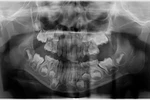

Jaw Cysts

Implant Treatment